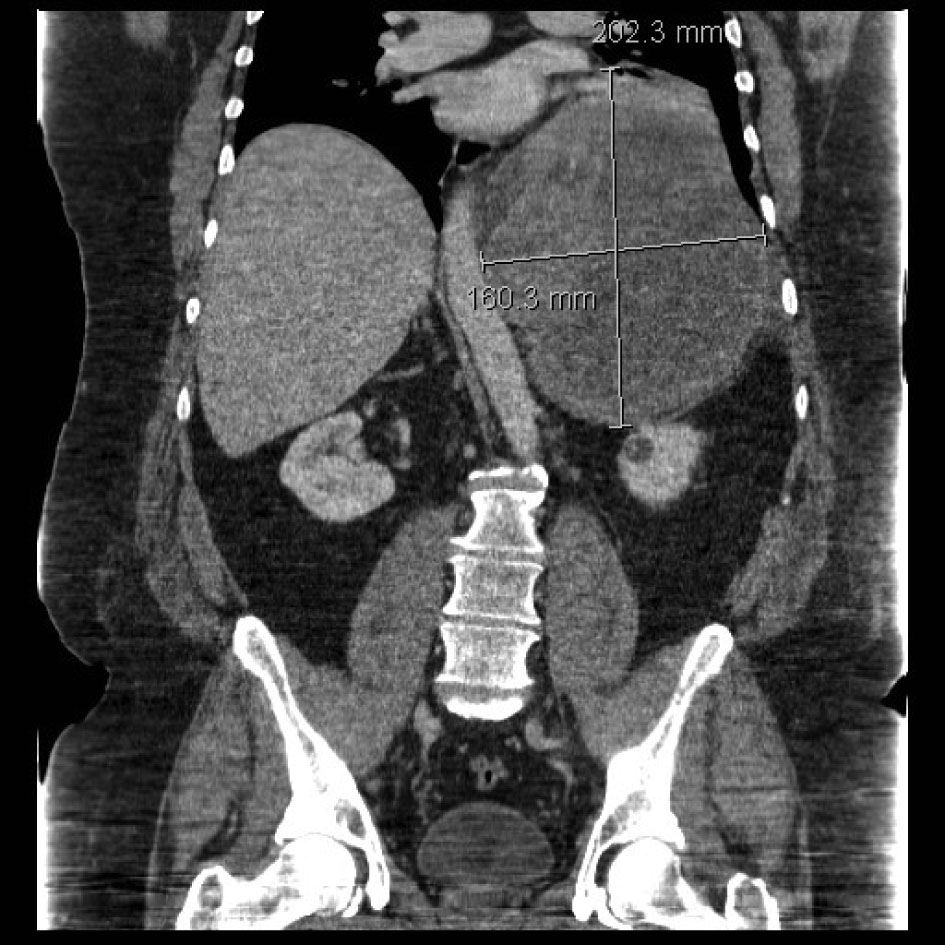

A 47-year-old obese man with severe mid-back pain for 6-months was found to have a large intra-thoracic mass on a routine plain film of the chest. A computed topography (CT) scan of the chest/abdomen/pelvis revealed a 20.5 × 15.5 × 16.0 cm heterogeneous mass in the left posterior mediastinum with effacement of the left lower lobe, left inferior pulmonary vein, displacement of hemi-diaphragm inferiorly and mediastinal structures towards to the right chest (Fig. 1). A magnetic resonance imaging (MRI) study revealed peripheral enhancement and internal necrosis (Fig. 2). CT-guided biopsy revealed a spindle cell tumor. Surgical resection was recommended.

![]() Click for large image | Figure 1. CT scan showing posterior mediastinal mass. |